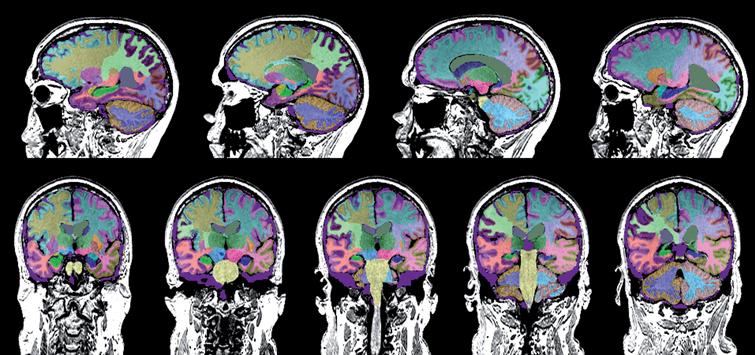

تصویربرداری شناختی تصویربرداری شناختی از بسیاری جهات انقلابی در مطالعه علوم اعصاب شناختی ایجاد کرد ، رشته ای که سعی در تعیین مکانیسم های عصبی فرآیندهای شناختی دارد. مطالعات اولیه در مورد روابط مغز و رفتار ، به یک آزمایش دقیق عصبی متکی بود. ظهور تصویربرداری شناختی و ساختاری مغز ، ابتدا با توموگرافی رایانه ای و بعداً با تصویربرداری رزونانس مغناطیسی(ام ار ای) ، زمینه را برای محلی سازی دقیق آناتومیکی نقایص شناختی که پس از آسیب مغزی آشکار

نقشه برداری مغز

نقشه برداری مغز هنگام کار بر روی تومورهای مغزی ، جلوگیری از آسیب رساندن به نواحی مغزی که مسئول زبان ، حرکت و عملکرد حسی هستند بسیار مهم است. در حالی که می دانیم کدام قسمت های مغز مسئول این عملکردها هستند (و در کجاها واقعاً واقع شده اند) ، مغز هر فرد به اندازه کافی منحصر به فرد است که تغییرات جزئی وجود داشته باشد. بسته به نزدیک بودن تومور به هر یک از این نواحی ، ممکن است

Frontotemporal atrophy

Description: Kio Medical has developed an app to quantify the volumes of the right and left hippocampus, frontal lobes and temporal lobes, to help assess disease diagnosis and progression. The obtained values are framed in a normative database to be compared with healthy subjects of the same age and gender. This software can be used to diagnose and monitor patients with Alzheimer’s disease, mild cognitive impairment and frontotemporal dementia. Disease: Alzheimer’s disease Mild cognitive impairment (MCI) Frontotemporal dementia Related